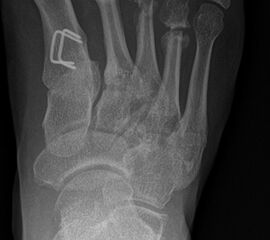

Wachstumslenkung mit moderner Klammer oder eight plate

Bei offenen Wachstumsfugen kann über eine Steuerung des Wachstums mit einer Klammer (Blount-Klammer/Flex Tack) oder kleinen Plättchen (Eight Plate) eine Korrektur von Achsabweichungen in der sagittalen und coronaren Ebene erreicht werden (Abb. 8). Der Hautschnitt beträgt ca. 1,5 - 2 cm und die so versorgten Kinder können ihre Extremität direkt postoperativ schmerzadaptiert voll belasten. Die wachstumslenkende Operation mit einer Klammer oder einem Plättchen besitzt ein enormes Korrekturpotential und erspart dem Kind oder Jugendlichen umfangreiche Umstellungsosteotomien und Plattenosteosynthesen, welche eine Schnittlänge von 15 cm und eine Entlastung des operierten Beines von 4-6 Wochen erforderlich machen.

Abb. 8 a-g: Genua vara prä- und postoperativ versorgt mit Flex Tacks (a-b) und ein Genu valgum versorgt mit Eight Plate an der medialen Femurkondyle (c); Spitzfuß bei congenitalem Klumpfuß und einem Flat Top Talus mit präoperativem Röntgenbild seitlich und der deutlich nach dorsal stehender Tibia(d); intraoperative Bilder der Epiphysiodese mittels Eight Plate zur Wachstumslenkung der distalen Tibia in die Extension (e-f) und postoperativer Verlauf nach sechs Monaten mit regelrecht stehender Tibia über dem Talus durch die distale Extension (g).

Zum Lesen der Bildbeschreibung und zur Vollansicht bitte die Bilder anklicken. Bilder: A. Helmers.